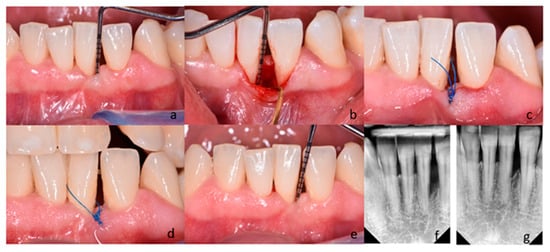

2.3. Clinical Examinations, Surgery, and Postoperative Care